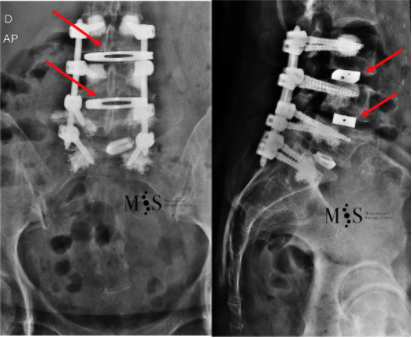

En estas dos imágenes se puede ver la corrección post-operatoria

de la escoliosis con sendas cajas OLIF (ver flechas rojas).